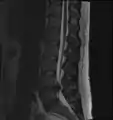

- Magnetic resonance imaging (MRI) without contrast is a diagnostic test that produces three-dimensional images of body structures using powerful magnets and computer technology. It can show the spinal cord, nerve roots, and surrounding areas, as well as enlargement, degeneration, and tumors. It shows soft tissues better than CAT scans. An MRI performed with a high magnetic field strength usually provides the most conclusive evidence for diagnosis of a disc herniation. T2-weighted images allow for clear visualization of protruded disc material in the spinal canal.

MRI scan of large herniation (on the right) of the disc between L4 and L5 vertebrae